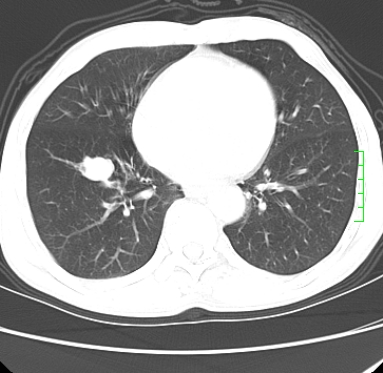

m,73y。膝关节疼痛伴双下肢水肿。入院常规胸片发现结节灶。增强为静脉期。

浅分叶、棘突,考虑右下肺周围型肺癌

考虑周围型肺癌  ,双上肺结核。

肿块周围可见局限性气肿,考虑肺癌可能性大。双肺上叶继发型肺结核。

指套征,强化明显,近侧肺组织局限性肺气肿,考虑支气管类癌,慢支、肺气肿、双上陈旧性tb、冠脉钙化。

鉴别:先天性支气管闭锁,变态反应性支气管肺曲霉菌病,肺癌,支气管囊肿,支扩黏液嵌塞。

1)考虑右肺下叶周围型肺癌。2)右肺上叶及左肺感染性病变(结核可能)。3)肺气肿。4)冠状动脉钙化。